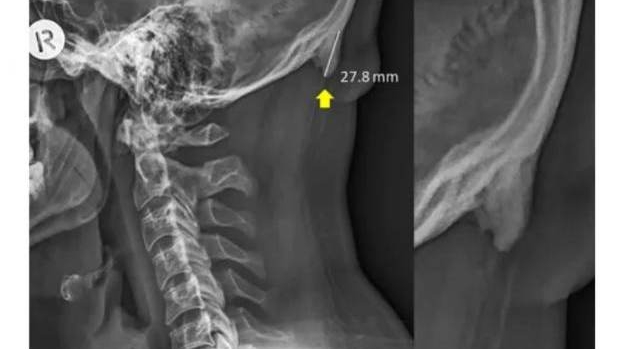

Австралийские ученые установили, что смартфоны провоцируют рост определенных костей черепа - роговидных шипов, представляющих собой костные наросты на задней части черепа. Они начинают образовываться из-за слишком частых наклонов головы.

В норме его длина не должна превышать трех миллиметров. Ученые изучили рентгеновские снимки 1200 добровольцев и пришли к выводу, что почти у 41% людей в возрасте до 30 лет размер шипа составляет от десяти до 31 миллиметра. Чаще всего "рога" встречались у мужчин.

Раньше такие наросты находили у пожилых людей, которые большую часть жизни занимались тяжелой физической работой. Пациенты испытывали хронические головные боли и неприятные ощущения в шее. Роговидные шипы у добровольцев не доставляли им дискомфорта. Их возникновение ученые связали с возросшей нагрузкой на мышцы шейно-черепного отдела из-за использования смартфонов, а не с генетической болезнью или последствиями перенесенных травм.